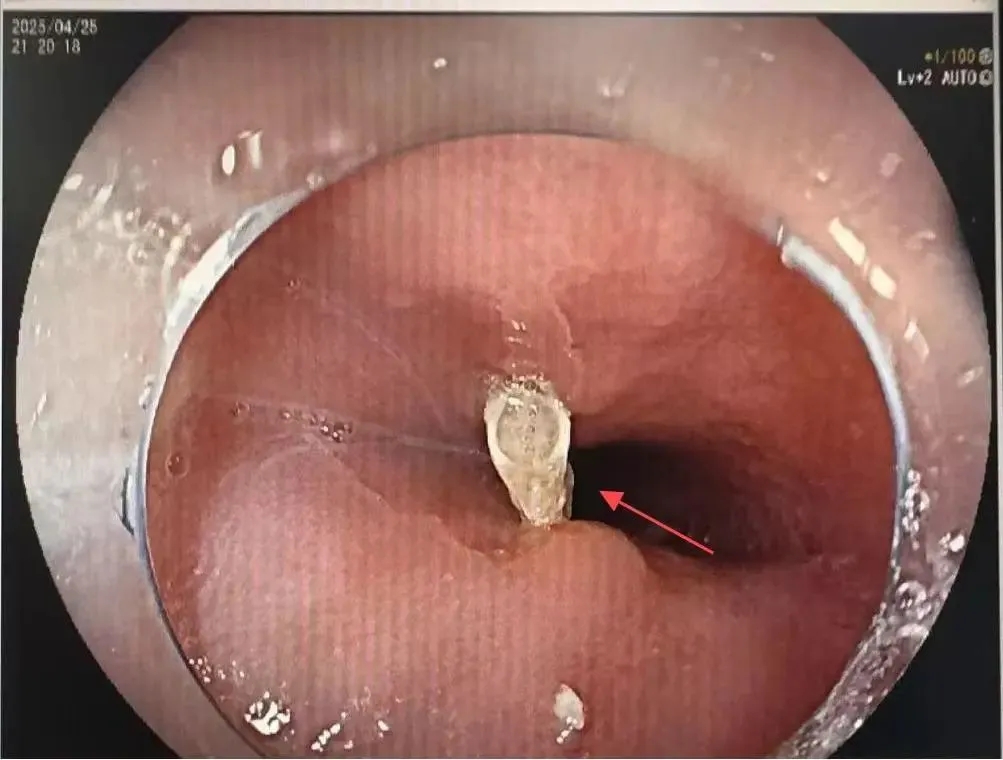

医生评估异物为“Y型鱼骨”,一上一下地深深刺 入了食管的左、右侧壁(见图2.1、图2.2)。他们选择了合适的透明帽及异物钳进行操作。

图2.1刺入食管鱼骨(红色箭头)

图2.2刺入食管鱼骨(红色箭头)